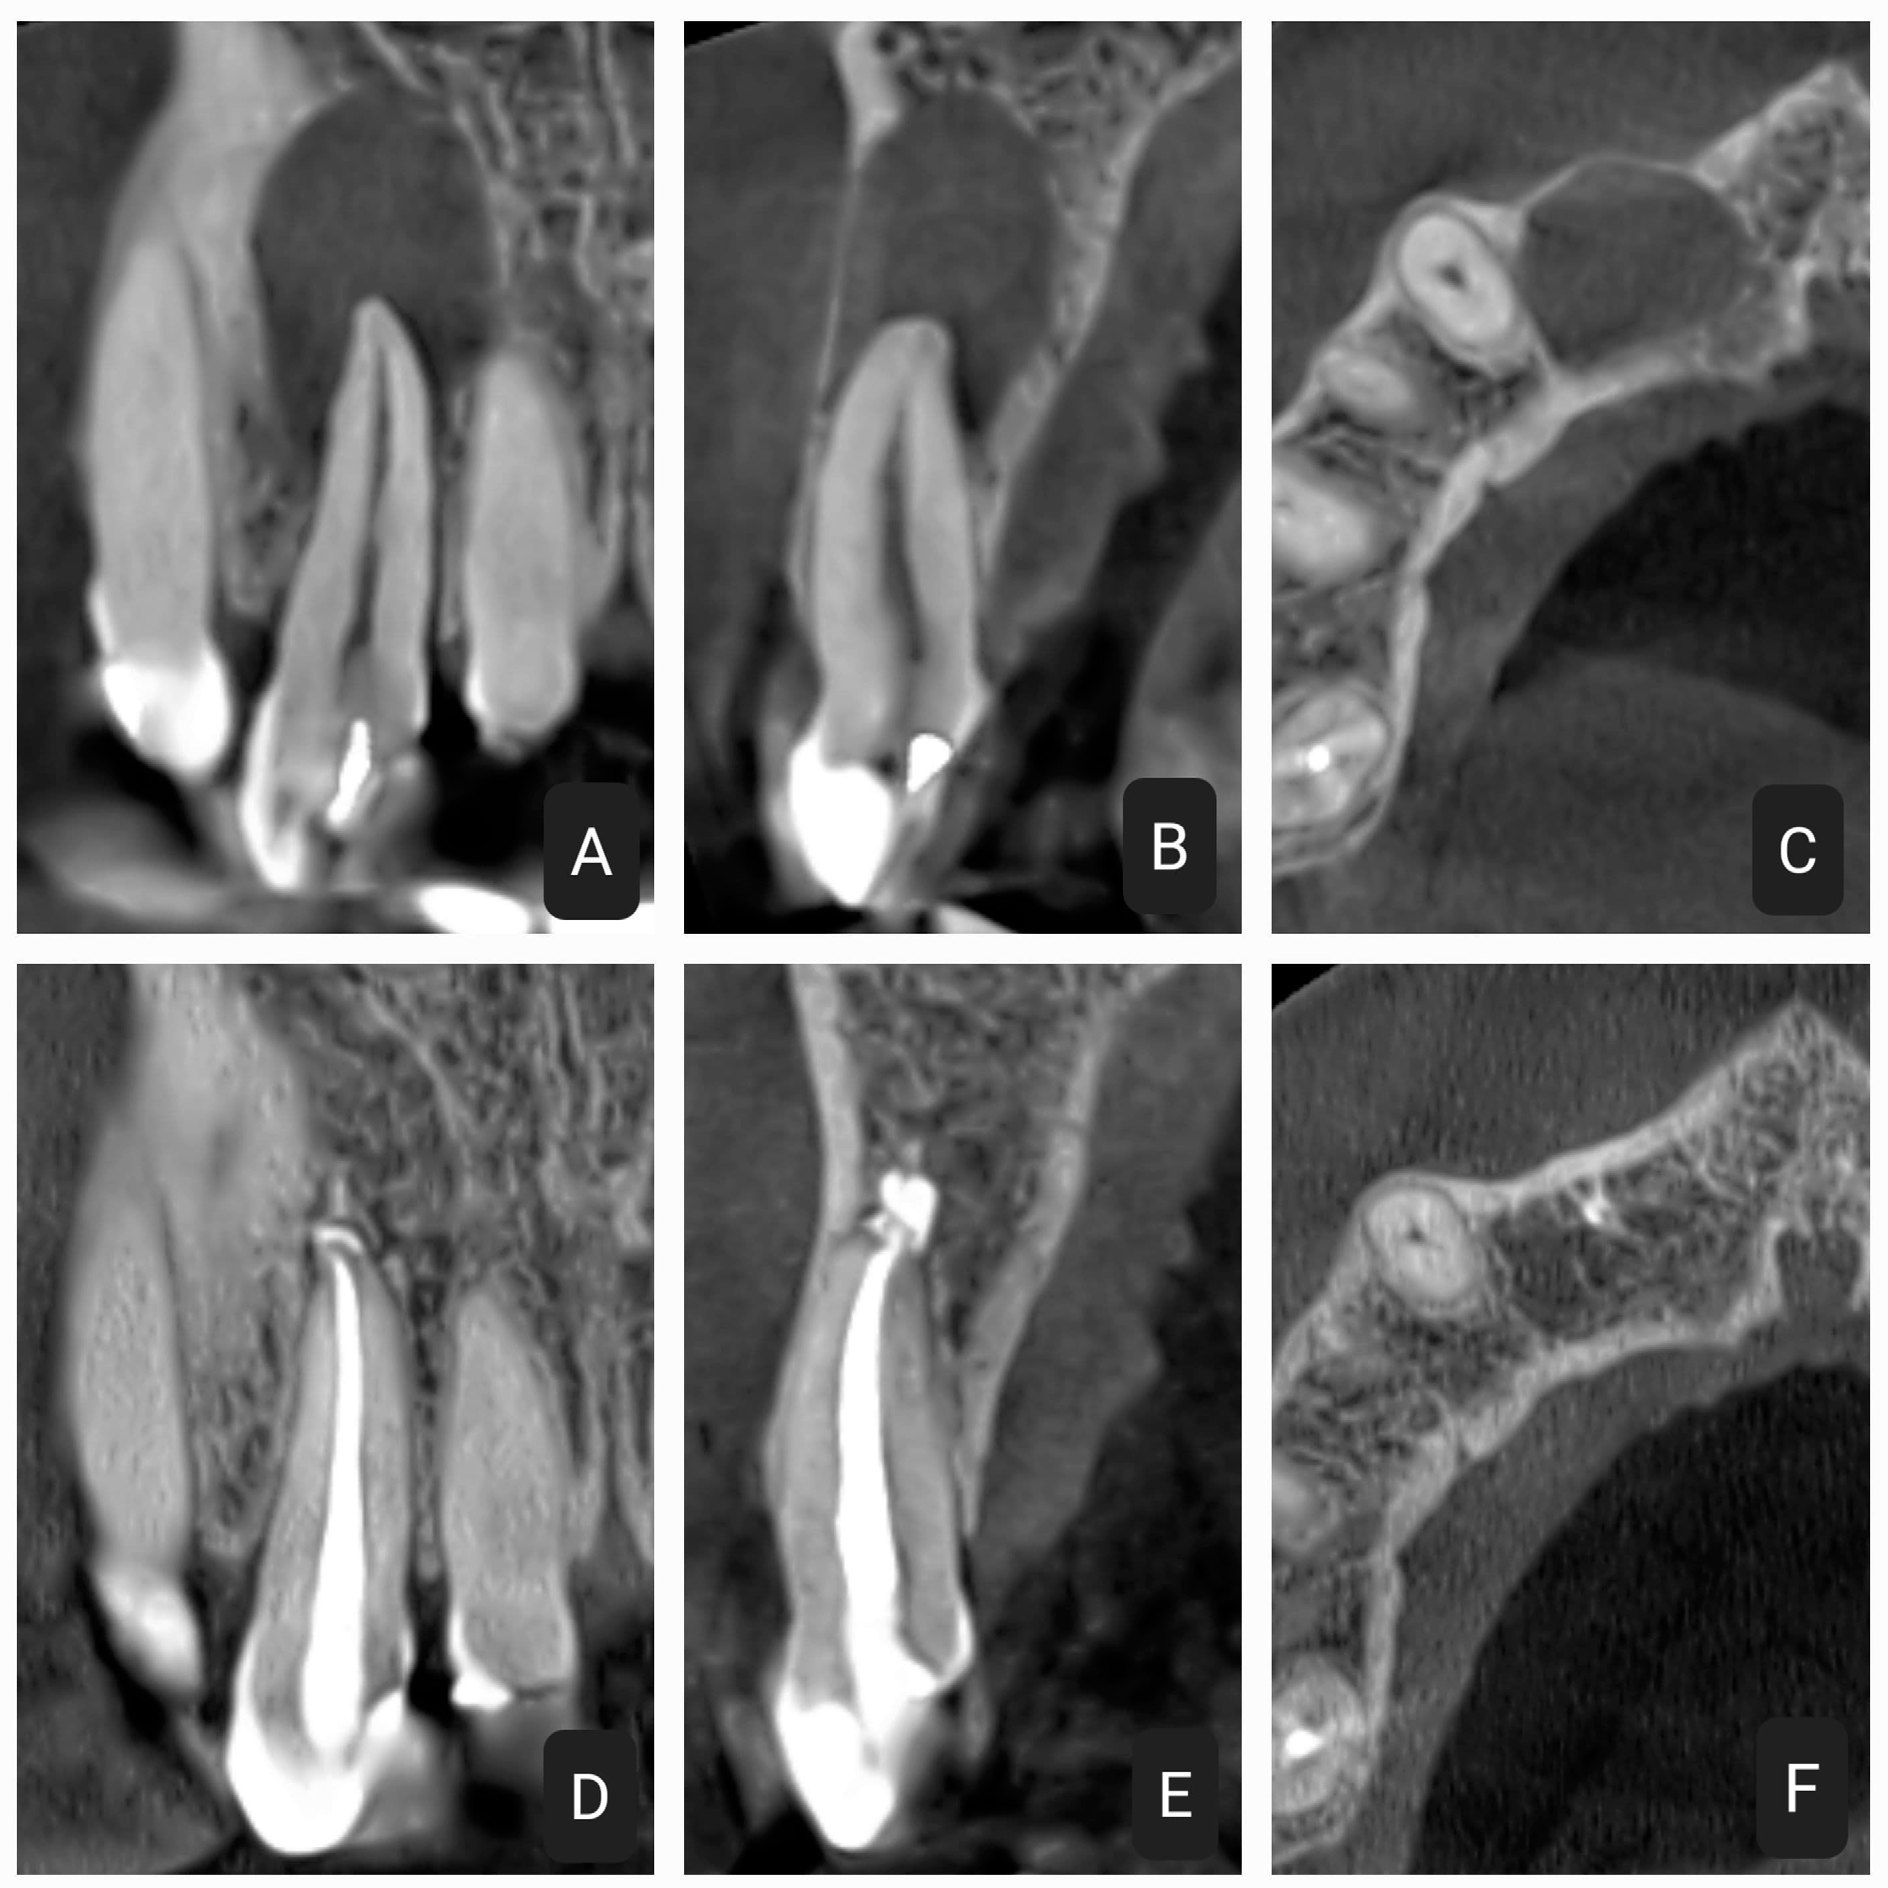

2.1. First Case

2.2. Second Case

2.3. Third Case

2.4. Fourth Case

2.5. Fifth Case